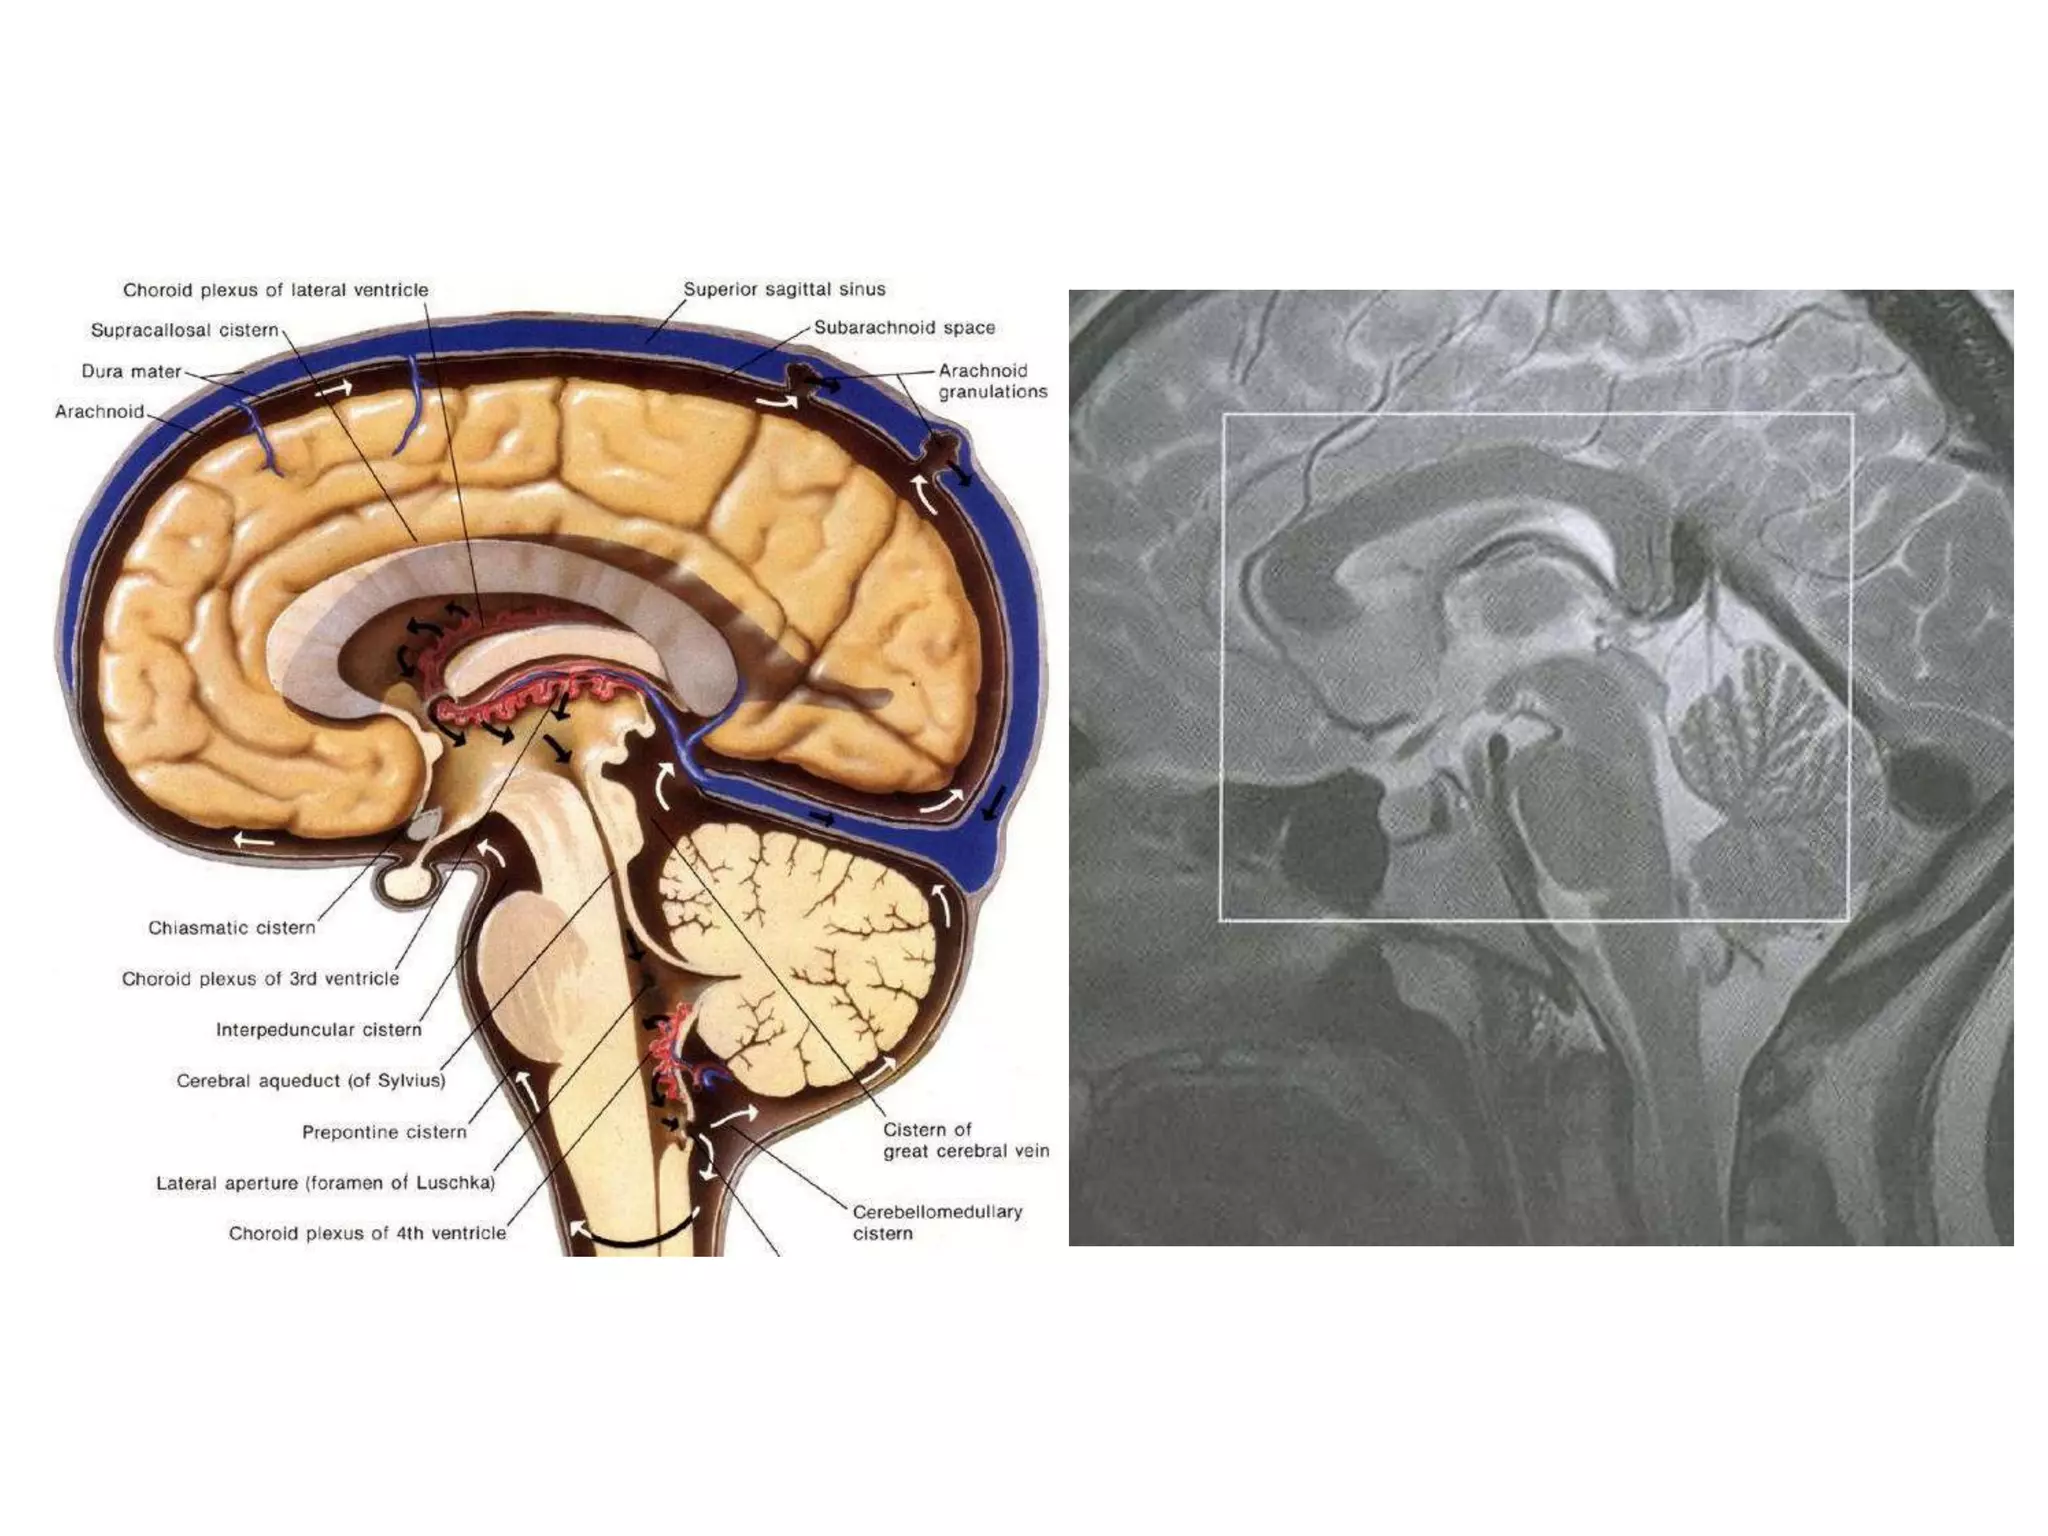

CISTERNS

• Where brain and skull are not closely

apposed, arachnoid and pia separate – and form

cisterns .

• Mainly present at base of brain, around brain stem and

free edge of tentorium.

1.   Posterior fossa cisterns

2.   Basal cisterns

3.   Mesencephalic cisterns

4.   Lateral superior cisterns

POSTEROR FOSSA CISTERNS

1. Medullary cistern : antr. to medulla

VA, spinal A, 12th nerve

2. Pontine cistern : b/w pons & clivus

vertibrobasilar A, AICA & SCA origin, 6th nerve

3. Cisterna magna : b/w medulla & postroinfr. cerebellum

PICA, 9th 10th 11th cranial nerves

(Triangular in saggital section)

4. Supr. cerebellar cistern : b/w tentorium & cerebellar H

SCA, supr. vermian veins.

5. CP angle cisterns : bounded by cerebellum, pons and

tentorium.

AICA, 5th 7th 8th cranial nerves

SUPRASELLAR / BASAL CISTERNS

1. Interpeduncular cistern : b/w Cerebral peduncles

Basilar A, thalamoperf. A .

2. Chiasmatic / Suprasellar cistern : above sella

ICA, MCA & ACA origin, P comm. A,

antr. Choroidal A; prox. basal V of Rosenthal;

optic chiasma & tract; hypothalamus, infundibulum.

(extends from infundibulum to postr. surface of frontal

lobe and lies b/w uncus on either side.

Contains circle of willis and so SAH seen)

MESENCEPHALIC CISTERNS

1. Ambient cistern : surrounds mid brain. Connects

Suprasellar, pontine & quadrigeminal cisterns.

PCA, BA, SCA, 6th cranial nerve .

2. Quadrigeminal cistern : behind pineal & Q plate

Connects ambient and supr. cerebellar cisterns.

Pineal gland, postr 3rd ventricle, V of Galen, V of Rosenthal.

3. Velum interpositum : above 3rd ventricle; below fornix

& C.callosum (antr. continuation of Quadrigeminal

cistern)

Internal cerebral V, Choroidal arteries .

CSF SPACES

• Choroid plexus

mainly in lateral ventricles and partly in 3rd and 4th

ventricles.

Choroid plexus within the atrium of lateral ventricle

and occasionally in 4th ventricle –

‘HYPO’ on CT and MRI.

On CECT, there is homogenous enhancement of choroid

plexus.